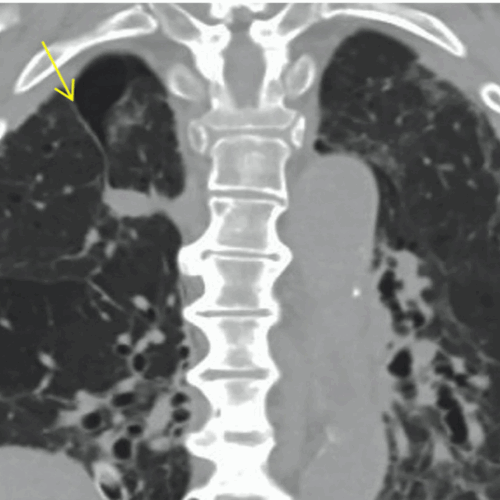

Case 3- Congenital Azygos Lobe

An azygos lobe is a rare normal anatomic variant of the right upper lobe, first described by Heinrich Wrisbergin 1778 due to invaginationof the azygosvein and pleura during development in the fetus.